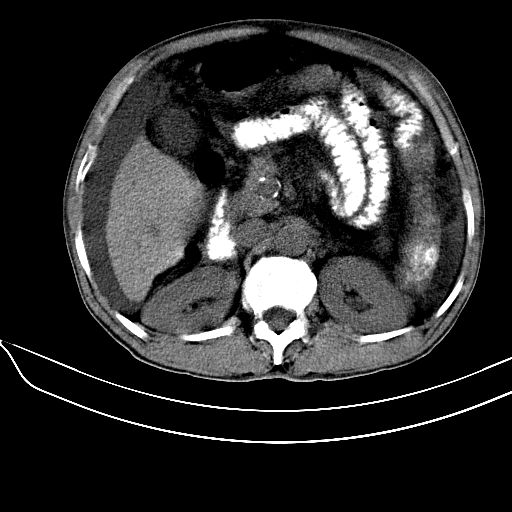

肝硬化可以明确,至于脾脏轻度增大,内部见大量钙化,考虑:脾脏感染性病变(脾脏脓肿,寄生虫或爱滋病等. )后的改变可能性大.

肝硬化明确,同意11楼是否做pse了。不然该考虑血液系统疾病了。血吸虫暂不考虑,1,肝肠无明显钙化。2,钙化形态该为条片状。

肝硬化、腹水,脾广泛不均匀高密度影原因?应密切结合病史,病人有没有感染史及造影史?如果都没有可考虑脾海绵状血管瘤钙化。

脾脏钙化多由炎症或结核引起,寄生虫卵或钙质沉积亦可导致,等等。